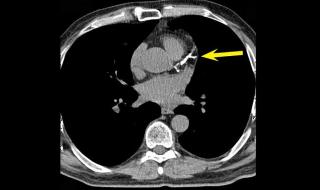

في توضيح طبي، أشار استشاري أمراض القلب الدكتور خالد النمر، إلى أن رقم تكلّس الشرايين (Calcium Score) غالبًا ما يرتفع تدريجيًّا مع التقدم في العمر، ووجود عوامل مثل ارتفاع ضغط الدم والسكري والتدخين، مؤكدًا أن الزيادة البسيطة لا تعني بالضرورة تدهور الحالة الصحية.

وضرب "النمر" مثالًا بأن من كان لديه رقم تكلّس 30 وأصبح 52 بعد 4 سنوات، فإن هذه الزيادة تُعد طبيعية ومتوقعة، إذ إن المعدل السنوي المقبول عادة لا يتجاوز 20 إلى 25٪.

وشدد على أهمية السيطرة على العوامل المسببة مثل الضغط، والكوليسترول، والتدخين، والوزن، حتى لا تتسارع نسبة التكلّس وتؤثر على صحة الشرايين.